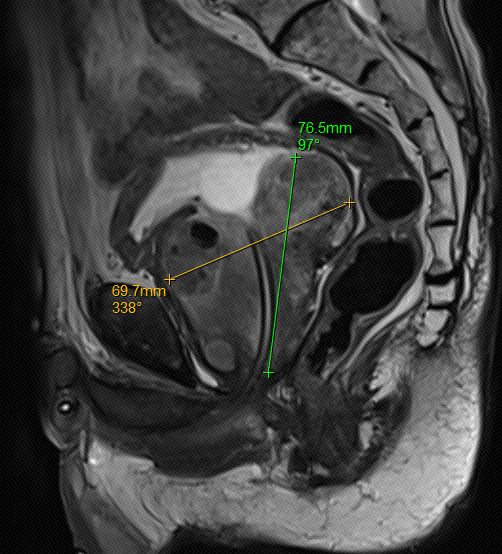

近日,我科完成一例机器人辅助腹腔镜下巨大前列腺根治性切除术。患者为75岁男性,半年前因PSA异常升高(115ng/ml)来院就诊,检查盆腔增强MRI提示前列腺增生(约237ml,为正常前列腺大小10倍左右)、前列腺外周带异常信号考虑前列腺癌可能,PI-RADS评分5分(预示前列腺癌80%可能),予行前列腺穿刺活检,病理确诊前列腺腺癌,Gleason评分5+5=10分。诊断明确,存在手术指征,因患者前列腺体积大,手术难度大,遂行内分泌治疗半年,复查MRI提示前列腺体积明显缩小(约143ml,仍为正常前列腺大小的6-7倍),近日全麻下行机器人辅助腹腔镜下前列腺根治性切除术,术中发现患者前列腺三叶增大,明显突入膀胱,手术过程顺利,术后第二天下床活动,术后第四天带尿管顺利出院。

前列腺矢状面(内分泌治疗后的前列腺体积缩小)